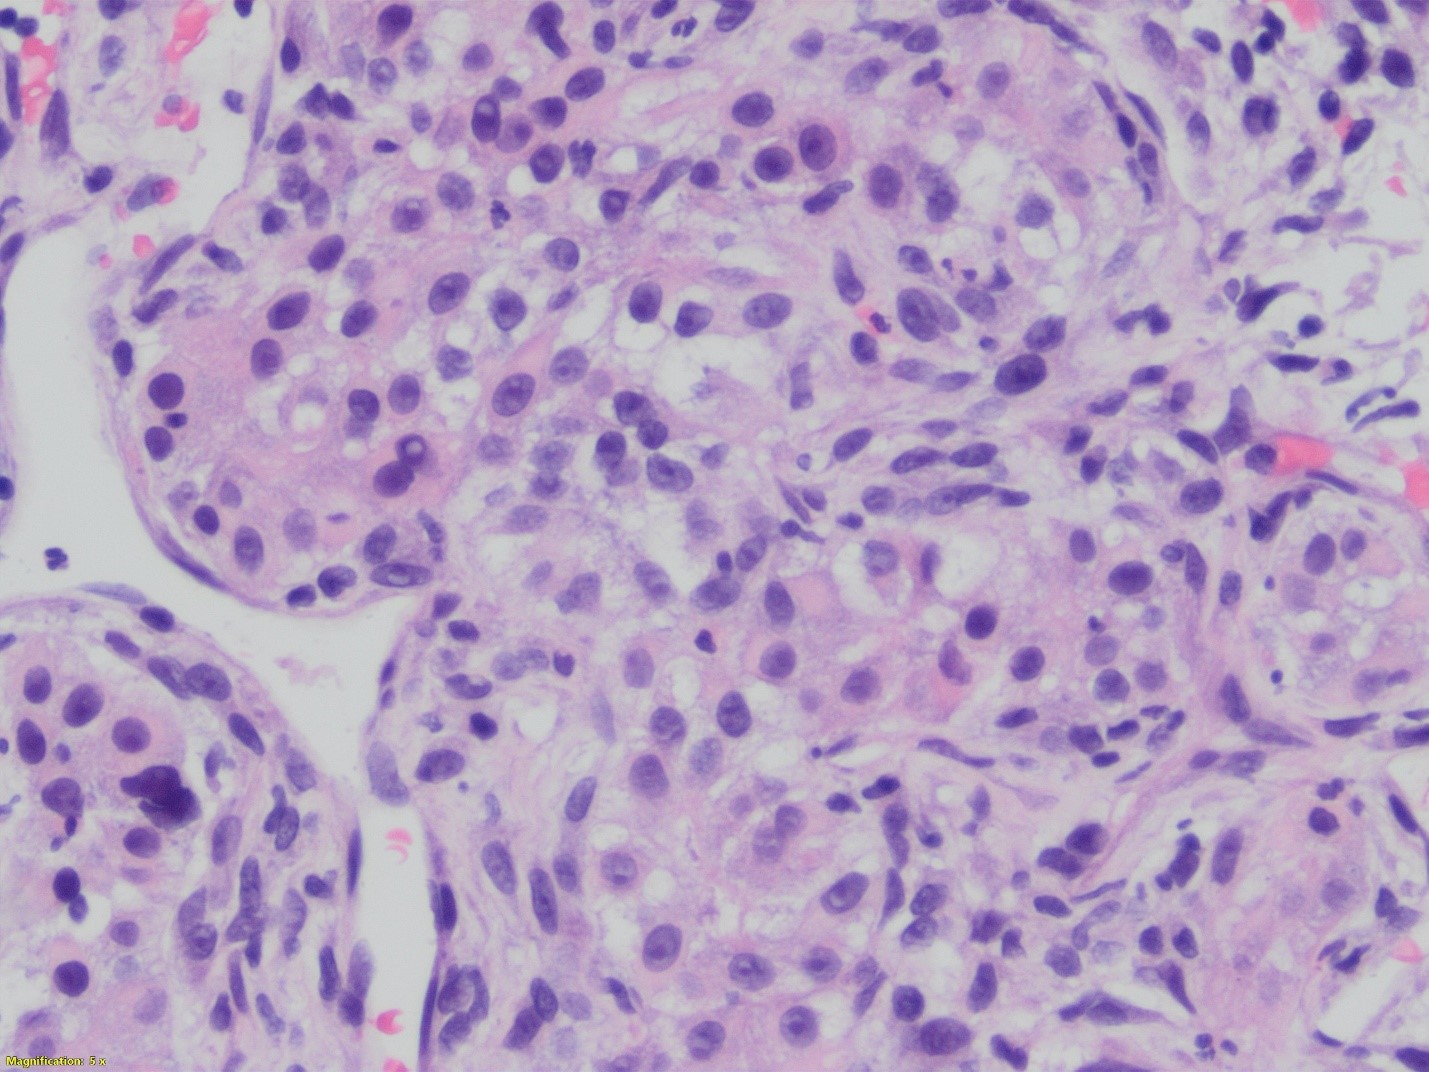

This unusual biphasic tumor has both carcinomatous and spindle cell component. The carcinomatous component is formed of granular, clear and markedly anaplastic cells. In some areas, the architecture recapitulates parathyroid differentiation: chief cells and oxyphil cells-like clusters. The areas that are poorly differentiated shows spindle and clear cell component. Keratin stain demonstrated the biphasic nature of the lesion. The tumor is positive for synaptophysin, and negative for calcitonin, Pax8, TTf-1, Sox10, and HMB45. Based on these immunostains and focal parathyroid differentiation a diagnosis of carcinoma with sarcomatoid features favoring parathyroid origin was rendered.